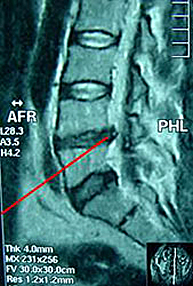

La configuración anatómica de una vértebra implica la existencia en su parte media de un orificio denominado agujero vertebral por cuyo interior discurre el sistema nervioso. La superposición de las diferentes vértebras origina que la suma de todos estos orificios constituyan el llamado canal lumbar. La disminución de sus diámetros constituye un cuadro patológico que se conoce como estenosis de canal lumbar.